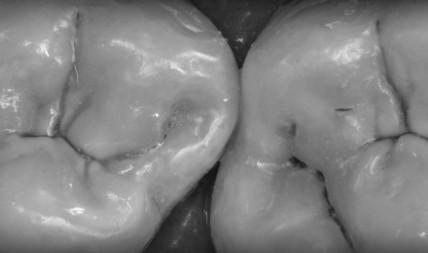

Непрямые композитные вкладки

122 Непрямые композитные вкладки. Детализированный разбор методики. Воспроизведение точной морфологии – является основной задачей при реставрации жевательных зубов, так как их функциональная нагрузка особо велика. Правильная анатомическая форма окклюзионных элементов обуславливает полноценное участие боковых зубов в акте жевания. Всякое качественное стоматологическое лечение заключается в гармоничном сочетании здоровья, функции и эстетики. В достижении всех этих целей […]